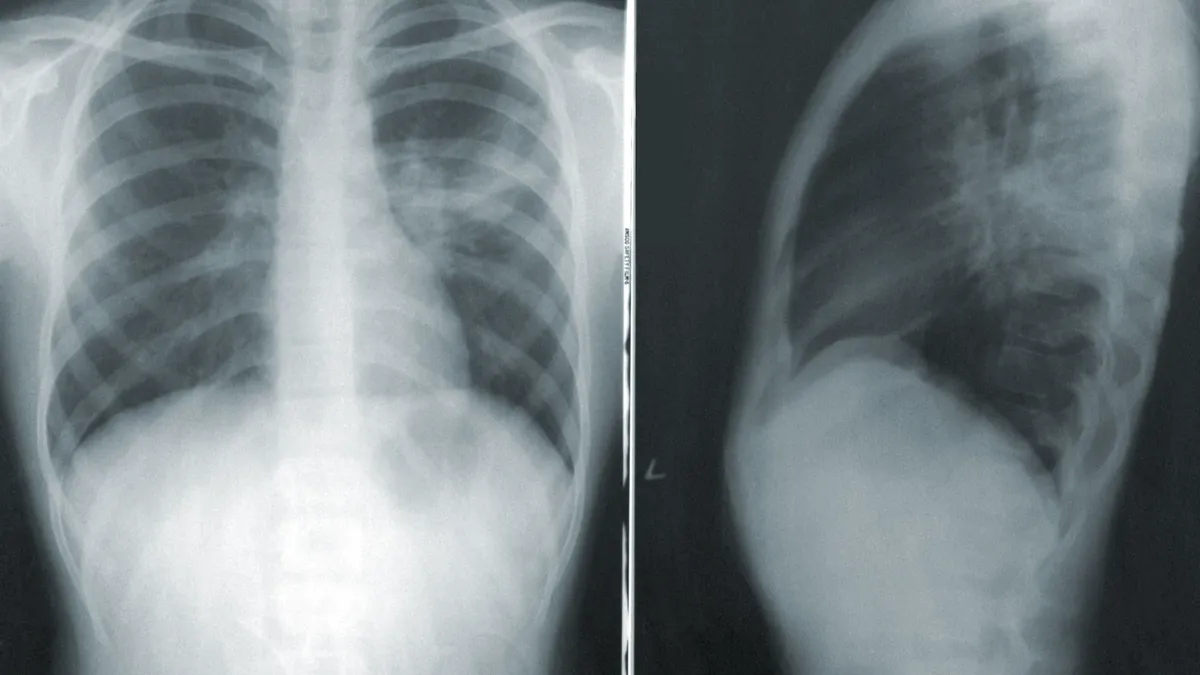

Фото: CDC / Unsplash